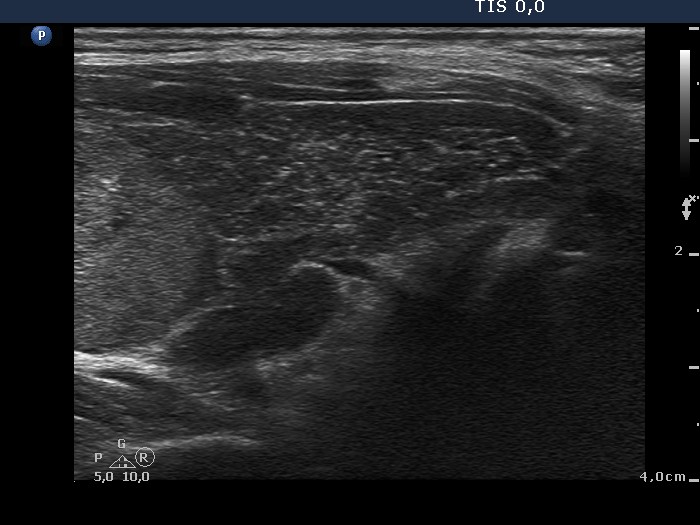

Consecutively operated patients with autoimmune thyroid disease - case 37 (conp 033) (ultrasonographic picture 7)

Lower part of the left lobe, longitudinal scan. Left (upper) the lower pole of the nodule, while right (lower) the extranodular part of the lobe.